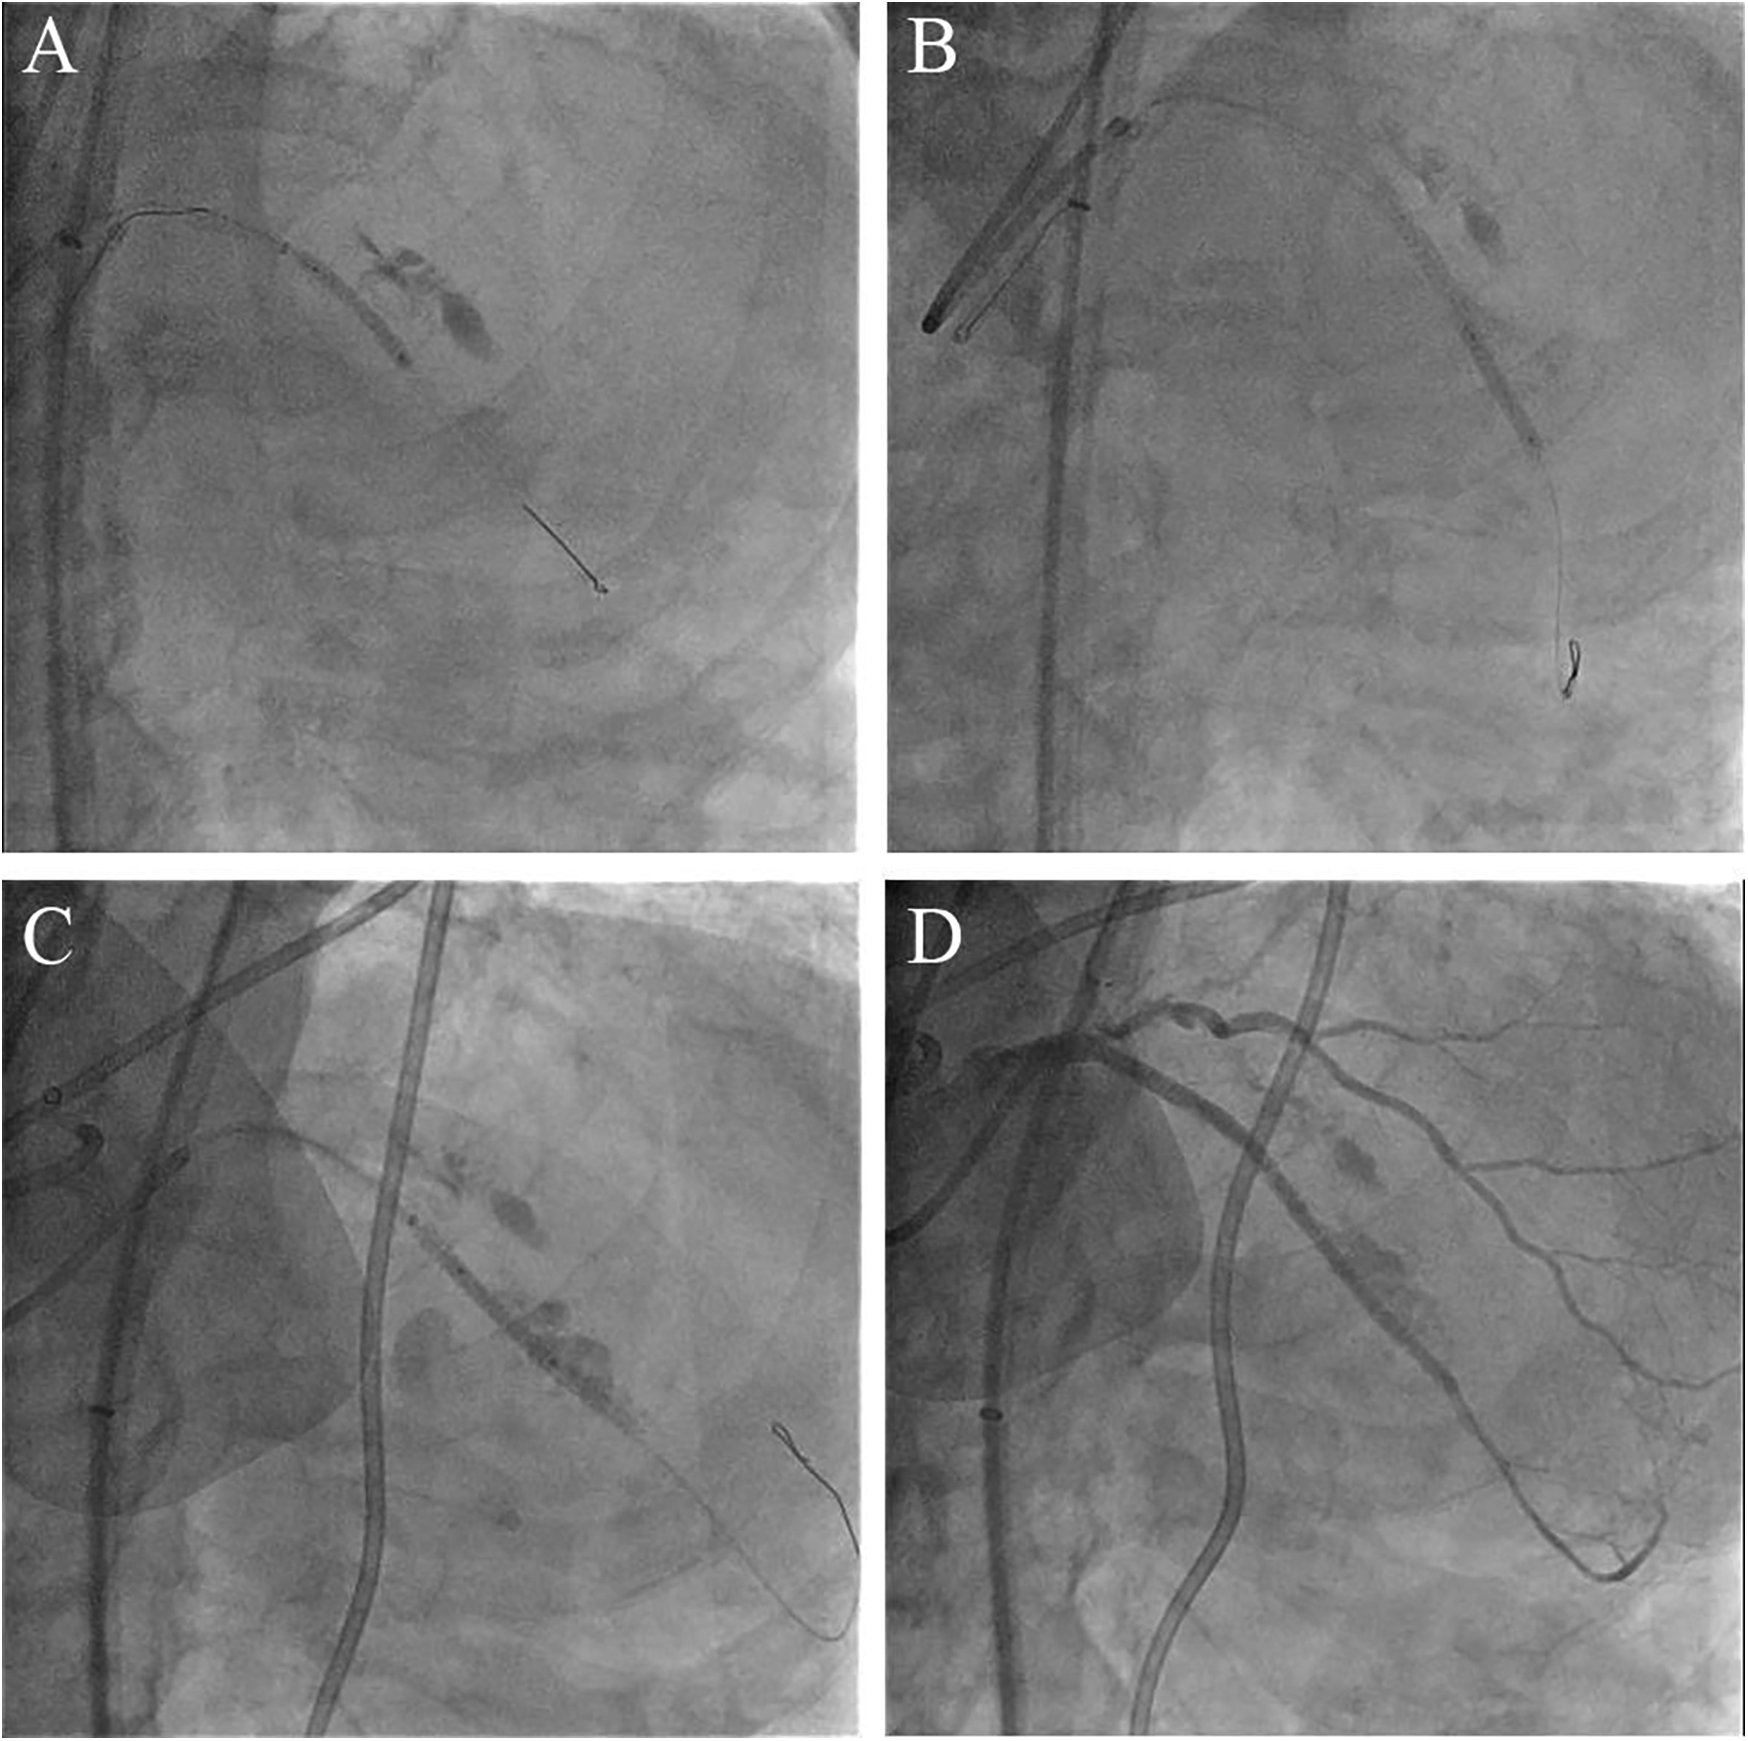

Figure 2

Bursting the balloon in the coronary artery with beyond-high-pressure inflation and subsequent coronary perforation. (A) Partial loss of contrast within the stent balloon following its rupture. (B) Complete removal of the ruptured stent balloon into the guiding catheter. (C) Large coronary artery perforation after the balloon burst.

Figure 3

Salvage procedure for coronary perforation employing the ping-pong technique. (A) The covered stent deployed at the proximal segment of stented LAD. (B) The second covered stent placed in the distal segment of stented LAD. (C) Final perforation closure with a third covered stent. (D) Angiogram after deploying three covered stents shows complete sealing of the perforation.

Coronary angiography, performed as part of an early invasive strategy, revealed a severely calcified chronic total occlusion (CTO)-like lesion in the proximal LAD and calcified stenosis of the ramus intermedius branch (Figure 1A). Right coronary angiography showed no significant stenosis, with CC grade 1 collaterals supplying the LAD via the epicardial and septal vessels. During two days of diuresis and stabilization, the patient's chest pain and dyspnea improved, and no dynamic ST-segment changes were observed. On day 3, PCI was performed according to the patient's preference. The laboratory findings on the day of PCI showed CK-MB 82 ng/ml and high-sensitivity Troponin I 13,138 pg/ml. Both common femoral arteries were accessed for PCI. An 8 F EBU 3.5 guiding catheter (Medtronic, Minneapolis, MN, USA) was used to engage the left main ostium. The LAD was successfully wired using the antegrade wire escalation technique, a commonly used approach in contemporary CTO PCI. (Escalation from Sion BLUE (Asahi Intecc, Japan) → Fielder XT-R (Asahi Intecc, Japan) → Ultimate Bros 3.0 (Asahi Intecc, Japan), with Corsair Pro XS (Asahi Intecc, Japan) microcatheter back-up.) 7F Guidezilla™ extension catheter (Boston Scientific, Natick, MA, USA) was introduced, and lesion preparation was sequentially performed using a 2.0 mm semi-compliant balloon followed by a 2.5 mm non-compliant balloon. Intravascular ultrasound confirmed the wire was in the true lumen throughout the LAD, revealing diffuse and calcified stenosis from the proximal to the distal LAD. Subsequently, a 2.5 × 46 mm Cre8™ EVO (Alvimedica, Istanbul, Turkey) drug-eluting stent (DES) was delivered and positioned across the mid-LAD lesion without resistance. During stent deployment, the dial on the pressure gauge window did not rise appropriately despite multiple adjustments to the indeflator handle. After approximately 15 attempts, we reached the rated burst pressure of 18 atm, achieving full stent balloon expansion (Figure 1B). However, retraction of the handle failed to deflate the balloon. Despite the dial indicating zero pressure and a strong tactile sensation of negative pressure when pulling back the handle, the stent balloon remained inflated with no signs of deflation. Our initial suspicion was a malfunctioning indeflator device. Therefore, we immediately switched to a new indeflator, filling the column with normal saline alone to dilute the contrast/saline mixture in the balloon catheter through slight inflation followed by full deflation. However, this also failed to deflate the balloon. We then attached a three-way stopcock connected to a 50 cc syringe to the balloon catheter and applied strong negative suction, but this also proved unsuccessful. After all efforts to deflate the balloon using negative pressure failed, we decided to attempt intentional balloon perforation using a stiff guidewire. A 7 F Judkins Left 4 (JL 4) guide catheter was inserted via the left femoral artery. The first EBU guide catheter was slightly withdrawn, and the JL 4 guide catheter was advanced into the left main. A Turnpike® LP microcatheter (Teleflex, Wayne, PA, USA) was used to deliver the wire. We attempted to puncture the inflated balloon with both the distal and proximal end of a Conquest Pro 12 and Astato® XS 20 wire (Asahi Intecc, Japan) multiple times (Figure 1C), but these attempts were unsuccessful. As the next step, we advanced the GuideZilla™ guide extension catheter deeply and attempted forceful retraction of the trapped stent balloon, which again failed (Figure 1D). Meanwhile, the patient developed severe chest pain and ST elevation on the electrocardiogram monitoring. His hemodynamic status deteriorated, necessitating the initiation of norepinephrine and dopamine. We contacted the cardiothoracic surgeon to discuss surgical options. To avoid delays in this critical patient, we decided to attempt ultra-high-pressure inflation of the balloon beyond its rated burst pressure as a last interventional resort. At 23 atm, the pressure dial suddenly dropped, and the contrast dissipated from the balloon, indicating a rupture (Figure 2A). The balloon was then successfully retrieved into the guiding catheter and removed from the coronary artery (Figure 2B). However, follow-up angiography revealed multiple Ellis grade III perforations in the stented LAD segment (Figure 2C). A 2.5 mm semi-compliant balloon was immediately inflated in the mid-LAD to plug the perforation. Despite prolonged inflation for 15 min, the perforation remained unsealed, necessitating the deployment of 3.5 × 19 and 2.8 × 19 mm GraftMaster covered stents (Abbott Vascular, Santa Clara, CA, USA) in the proximal and distal segments of the stented LAD using the Ping Pong technique (Figures 3A,B). As the patient's hemodynamic status remained unstable, an emergency pericardiocentesis was performed. Angiography still showed persistent extravasation in the mid-segment of the stented LAD, so an additional 2.8 × 19 mm GraftMaster covered stent was deployed (Figure 3C). After successfully managing the coronary perforation, a 3.0 × 33 mm DES was placed in the stenotic proximal LAD, followed by post-dilation with a 3.5 mm non-compliant balloon. Final angiography confirmed well-expanded stents with no dissection or residual perforation (Figure 3D). Fortunately, the patient was discharged after 19 days (including three days in the intensive care unit) and remained asymptomatic for two months. We initially planned to place him on lifelong dual antiplatelet therapy, but he was later transferred to an elderly care hospital and lost to follow-up.